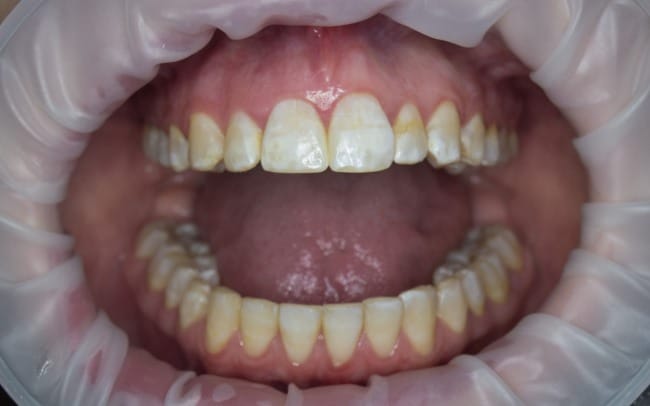

- Permukaan gigi tampak bercak putih, garis halus, atau bercak coklat

- Gigi terlihat kusam, rapuh, atau mudah patah

- Tekstur gigi terasa kasar atau tidak rata saat disentuh

- Pada kasus berat, gigi bisa berlubang atau tampak terkikis

Pada kasus seperti ini, gigi yang sedang tumbuh akan mengalami perubahan struktur dan warna. Akibatnya, permukaan gigi bisa tampak bercak putih, garis-garis, atau bahkan bercak coklat, tergantung seberapa banyak fluoride yang masuk ke tubuh selama proses pertumbuhan gigi berlangsung.